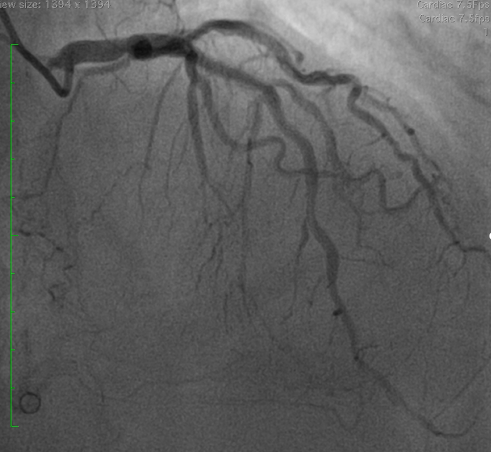

Coronary angiography demonstrated a patent LAD stent and CTO in-stent restenosis (ISR) at mid RCA with ipsilateral collateral flow from the RV branch to the PDA. Anatomical challenges included a proximal RV branch near the CTO cap, a nearly 90¡Æ CTO entry angle, a lesion length of ~60 mm, and distal bifurcation involvement. The CTO had a tapered stump with a visible microchannel. The J-CTO score was 2.

PCI was performed via single radial access with a 6F short-tip AL guiding catheter and Finecross microcatheter. 3D wiring with UB3 under orthogonal views; escalation to Gaia 3. Anchor ballooning in the RV branch improved support. The wire successfully crossed into the PLV. Predilation with a small balloon, followed by scoring ballooning. A Crusade dual-lumen catheter enabled Gaia 3 wiring into the PDA, which was predilated with a 2.5 mm balloon. IVUS revealed undersized and extensively malapposed stents contributing to ISR and prior very late thrombosis. High-pressure NC 3.75 mm ballooning improved expansion, though full correction was limited by the original stent size. A hybrid treatment strategy was chosen—DCB for both PLV and PDA (3.0¡¿20 mm and 3.0¡¿15 mm respectively, with DCB-assisted kissing), and DES reconstruction of the mid-to-proximal RCA using 4.0¡¿38 mm and 4.0¡¿20 mm stents delivered with guide extension support. Final IVUS confirmed optimal expansion and apposition without edge dissection. Final angiography showed TIMI 3 flow with no complications. At 9 months, angiography demonstrated patent RCA stents and positive remodeling at the PLV ostium.